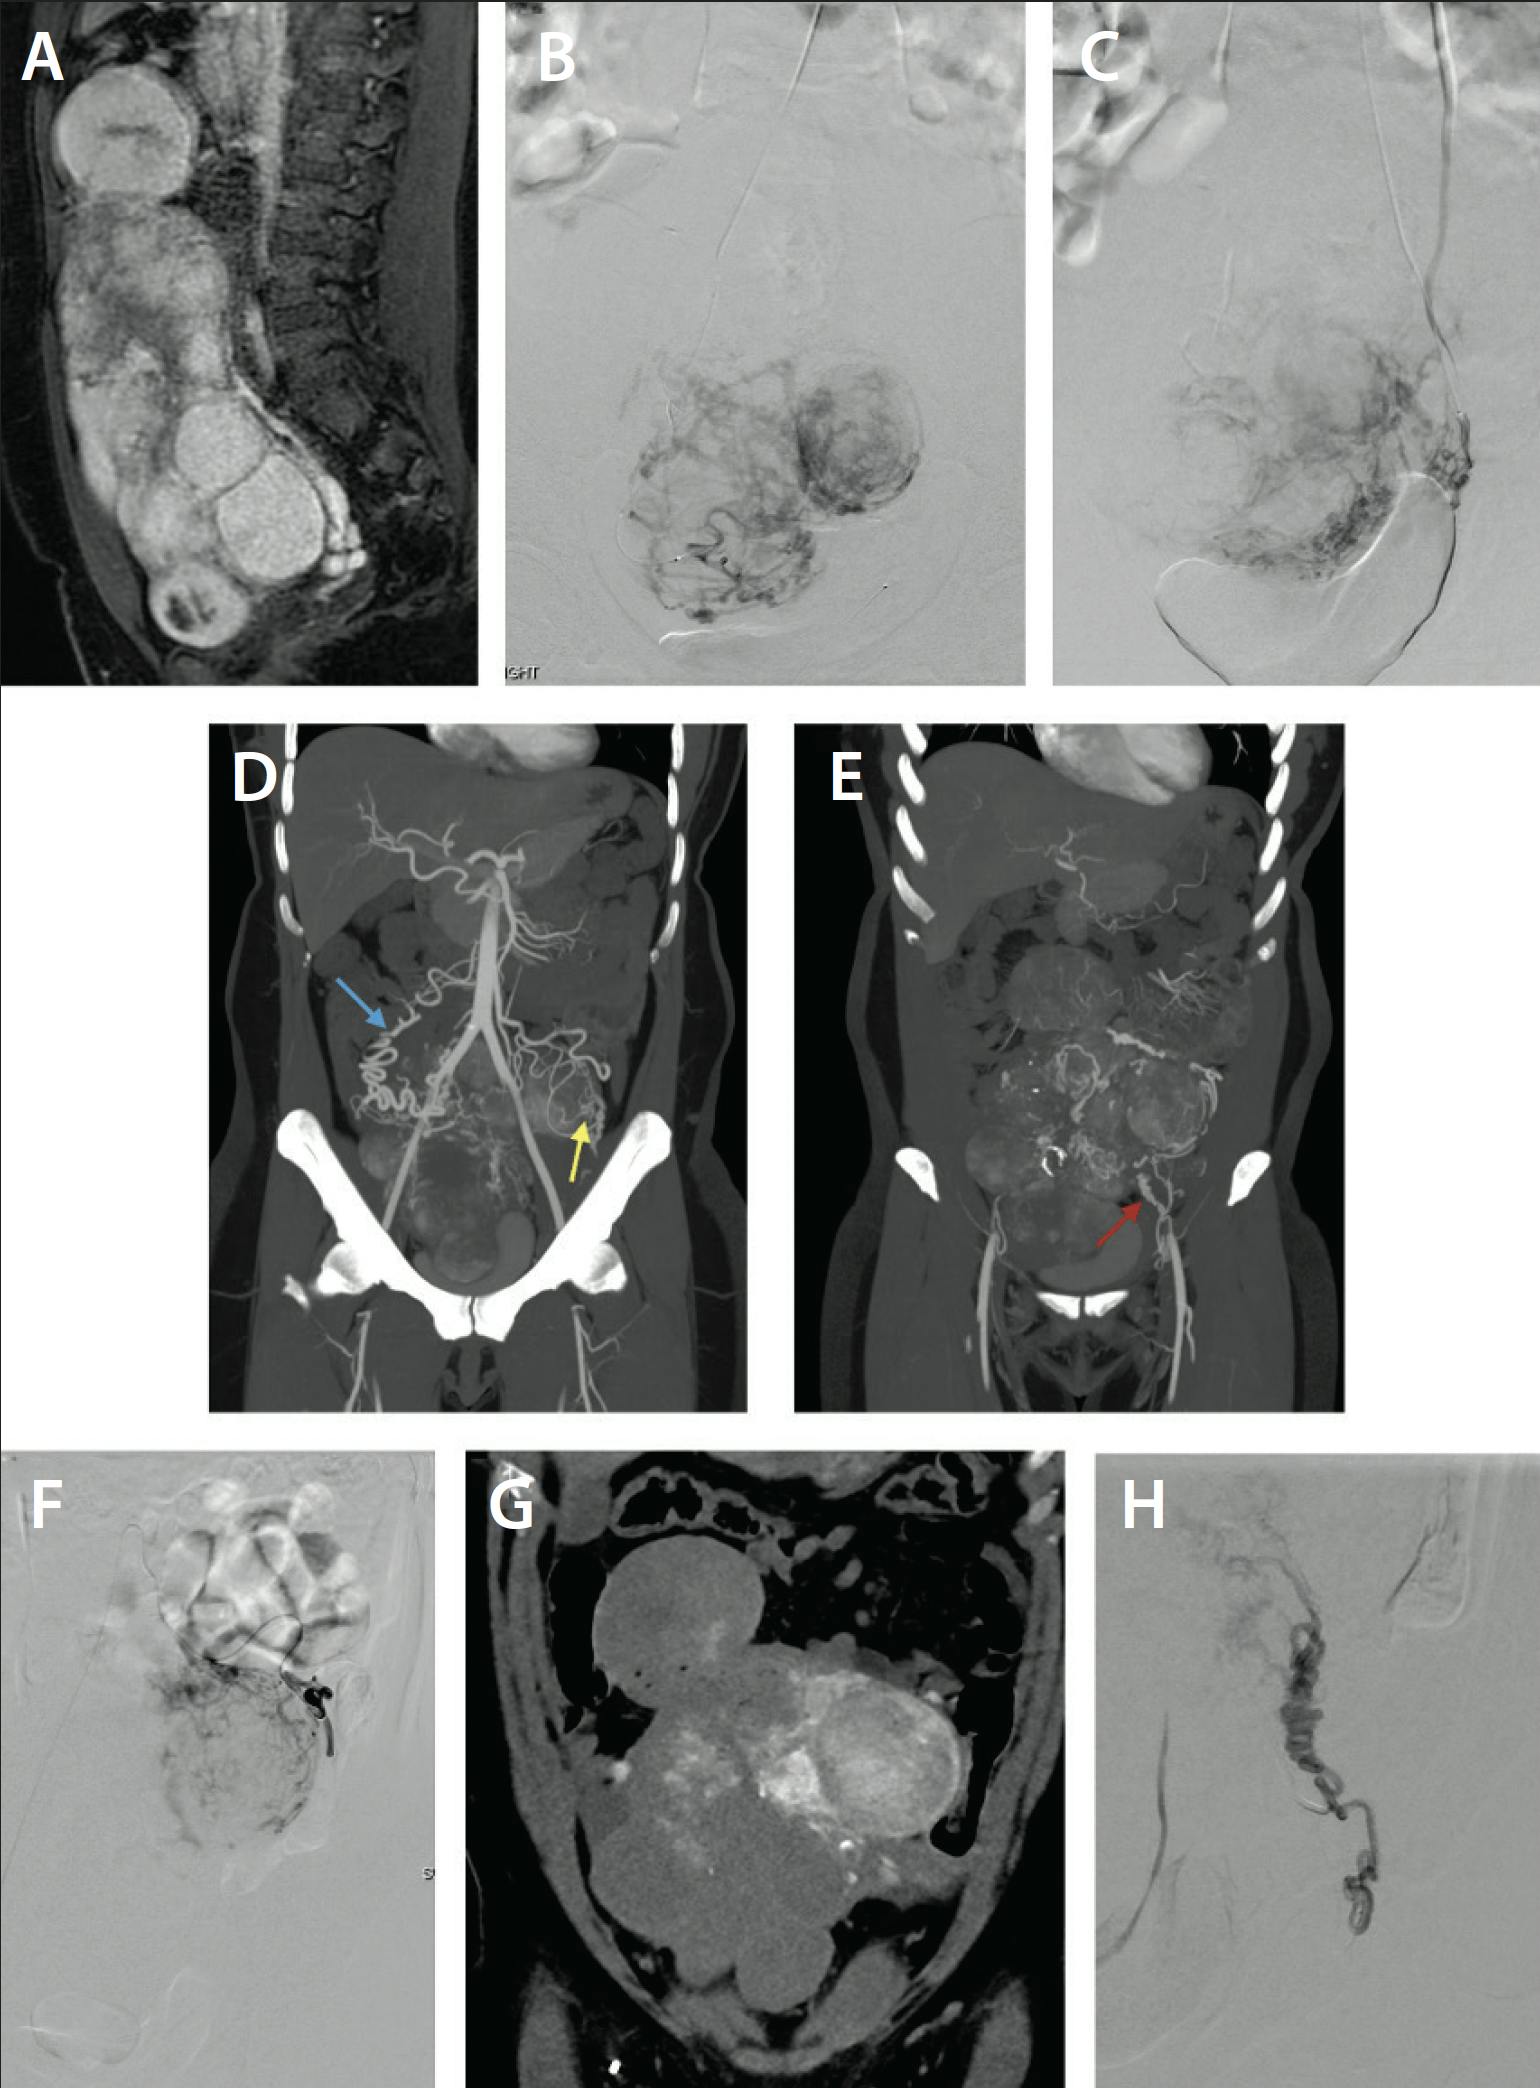

Mapping the vascular supply to fibroids is yet another way to tailor the treatment approach to the patient. Although preprocedure MRI is critical for evaluating uterine anatomy, it can also be used to evaluate common sources of collateral uterine blood supply like the ovarian arteries. For the small number of patients who report minimal or no symptom improvement postprocedure, additional collateral supply should be considered and patients could benefit from further evaluation with CTA, which would better delineate complex vascular collateral anatomy (Figure 1). A case report by Alabdulghani et al highlights the utility of intraprocedural CTA to demonstrate the extensive collaterals that could be additionally embolized for improved symptom control.28

Figure 1. A woman in her early 40s with preprocedure sagittal T1 MRI demonstrating enhancement of multiple uterine fibroids (A). Digital subtraction angiography (DSA) showed catheterization of the right uterine artery (B) and left uterine artery, with filling of inferior fibroids but not the complete uterus (C). CTA demonstrated collateral blood supply from right ovarian artery (D, blue arrow) and branch of inferior mesenteric artery (IMA; yellow arrow) and left round ligament artery (E, red arrow) to the fibroids. DSA showed selective catheterization of a branch of the IMA (F) and intraprocedural CTA confirmed filling of the fibroid without filling of the bowel (G). DSA showed selective catheterization of the left round ligament artery with filling of the fibroid (H). In total, the bilateral uterine arteries, right ovarian artery, a branch of the IMA, and a left round ligament artery were embolized.